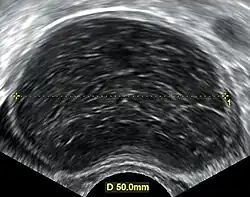

Transvaginal ultrasonography of a hemorrhagic ovarian cyst, probably originating from a corpus luteum cyst. The coagulating blood gives the content a cobweb-like appearance. -

Ovarian cysts are usually diagnosed by pelvic ultrasound, CT scan, or MRI, and correlated with clinical presentation and endocrinologic tests as appropriate.[15] Ultrasound is the most important imaging modality, as abnormalities seen in a CT scan sometimes prove to be normal in ultrasound.[5][8] If a different modality is needed, then MRIs are more reliable than CT scans.[5]

Ultrasound

Usually, an experienced sonographer can readily identify benign ovarian cysts, often with a level of accuracy that rivals other approaches.[5]

Follow-up imaging in women of reproductive age for incidentally discovered simple cysts on ultrasound is not needed until 5 cm, as these are usually normal ovarian follicles. Simple cysts 5 to 7 cm in premenopausal females should be followed yearly. Simple cysts larger than 7 cm require further imaging with MRI or surgical assessment. Because they are large, they cannot be reliably assessed by ultrasound alone; it can be difficult to see posterior wall soft tissue nodularity or thickened septation due to limited ultrasound beam penetrance at this size and depth. For the corpus luteum, a dominant ovulating follicle that typically appears as a cyst with circumferentially thickened walls and crenulated inner margins, follow up is not needed if the cyst is less than 3 cm in diameter.[8] In postmenopausal women, any simple cyst greater than 1 cm but less than 7 cm needs yearly follow-up, while those greater than 7 cm need MRI or surgical evaluation, similar to reproductive age females.[16]